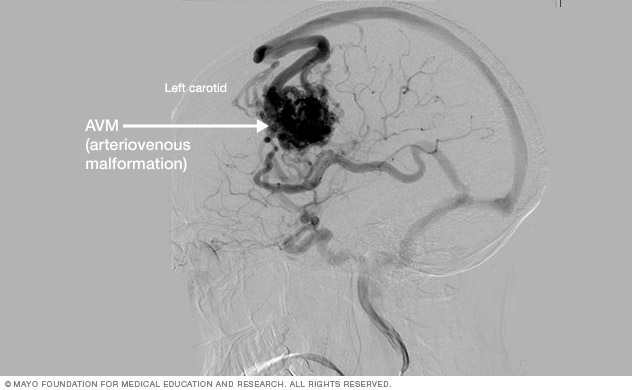

Cerebral angiography. This is the most detailed test to diagnose a brain AVM. Cerebral angiography reveals the location of the feeding arteries and draining veins, which is critical to planning treatment. Cerebral angiography is also known as cerebral arteriography.

In this test, a long, thin tube called a catheter is inserted into an artery in the groin or wrist. The catheter is threaded to the brain using X-ray imaging. A dye is injected into the blood vessels of the brain to make them visible under X-ray imaging.